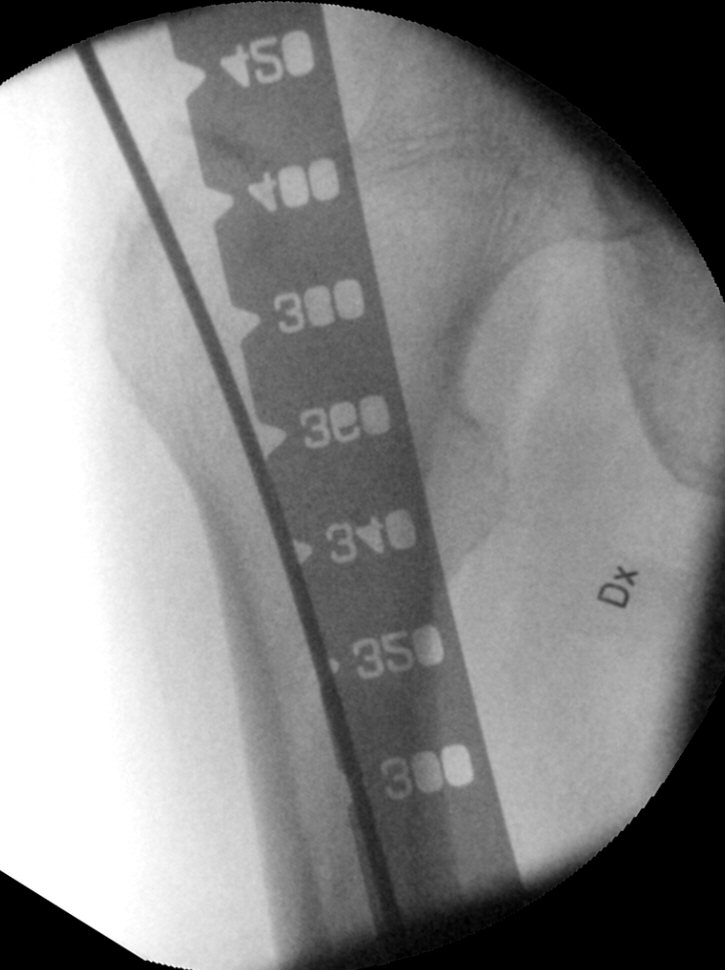

- Mät längd på märgspiken med speciallinjal, antingen genom att mäta hur mycket som sticker ut av guidevajern eller genom att hålla linjalen ovanför femur i genomlysning. Spiken ska gå från trokantern till kondylnivå, nästan ner till femurs distala ände, ungefär i nivå med patellas proximala pol.

Mätning av gammaspikens längd. Valde i detta fall 400 mm.